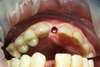

Avant